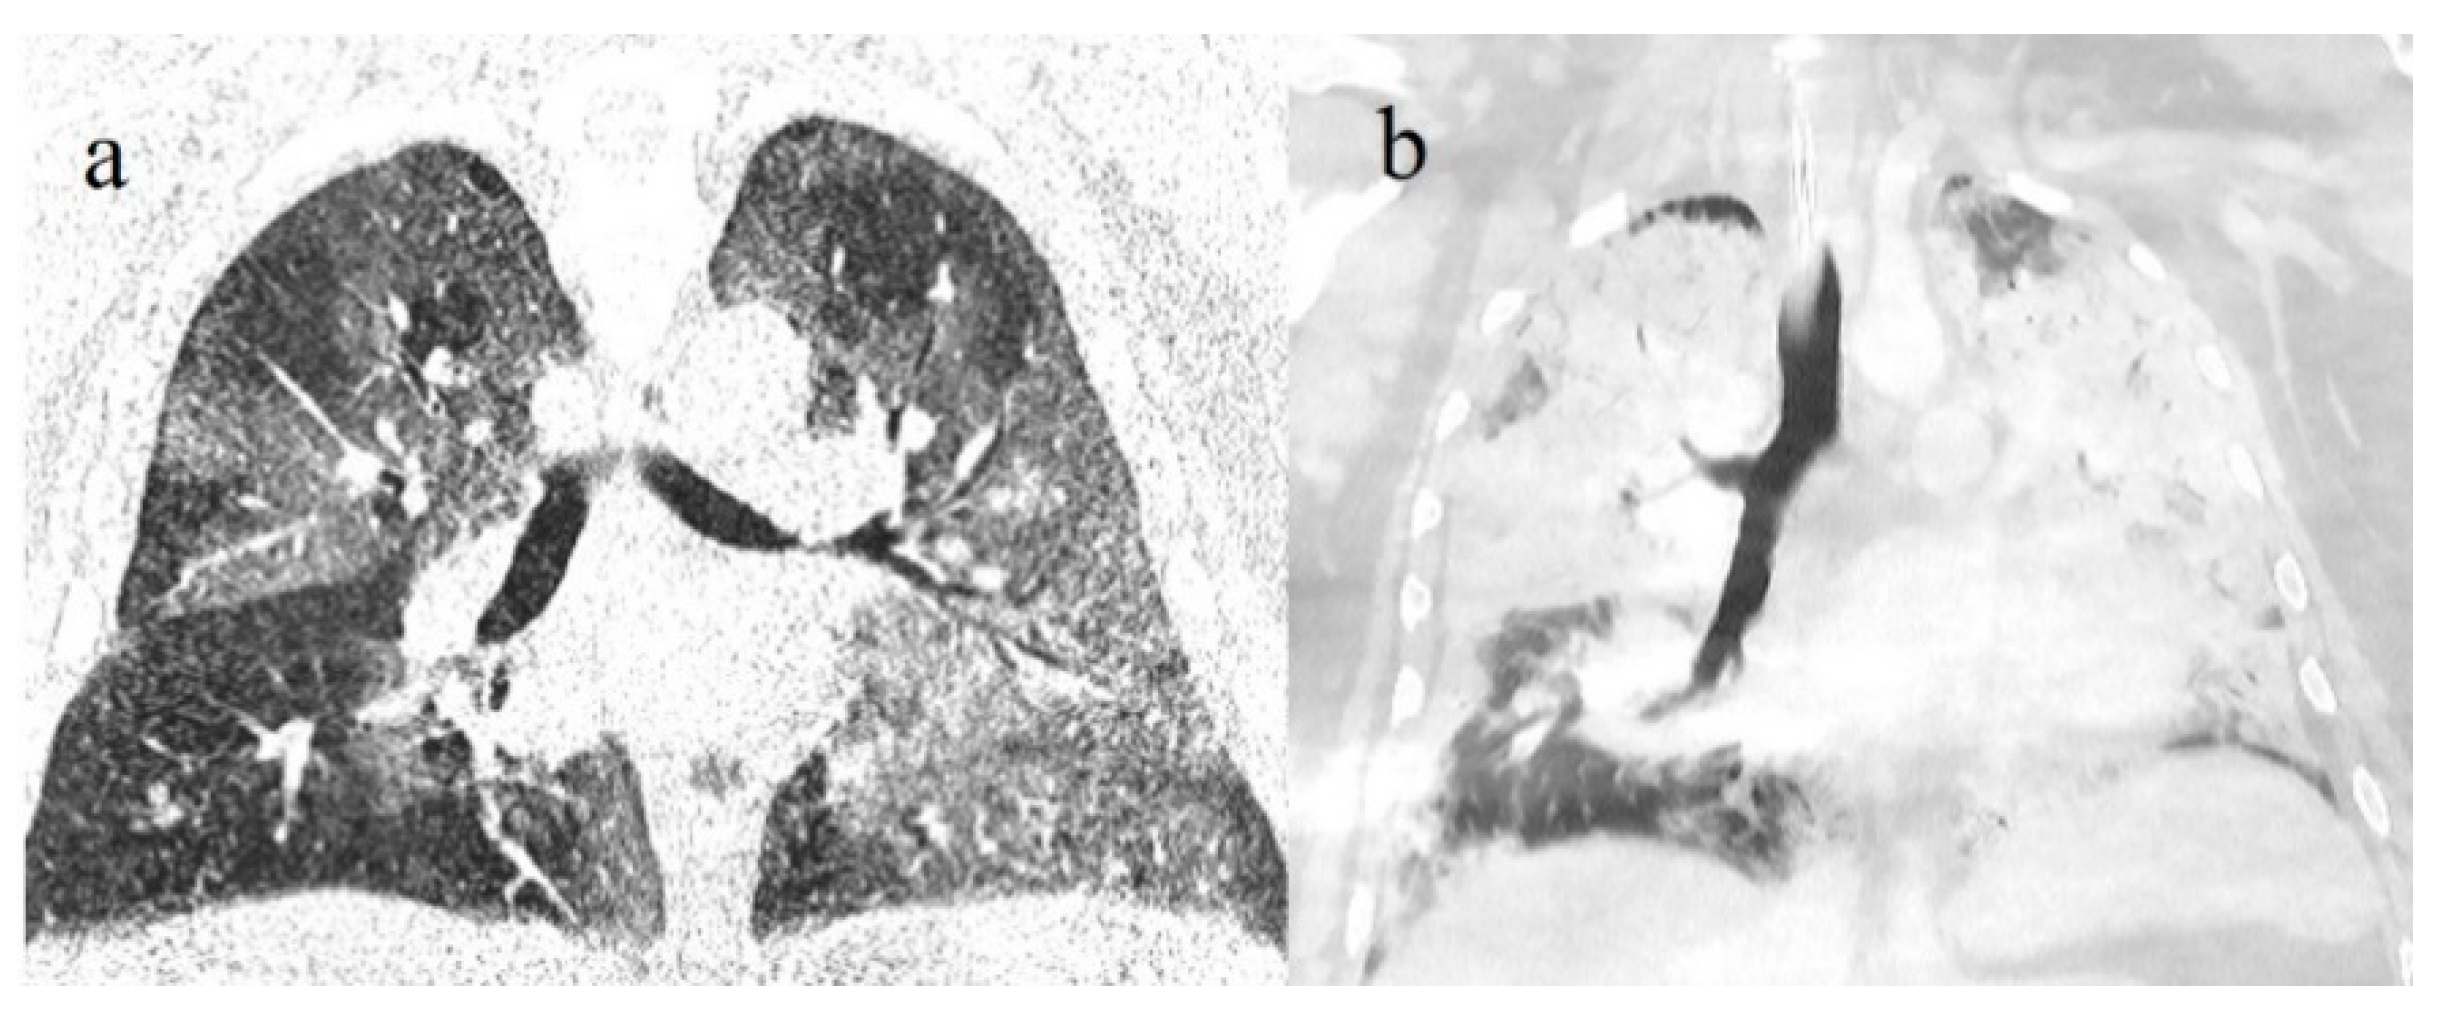

5. Imaging and Histopathological Correlations

- Henkel, M.; Weikert, T.; Marston, K.; Schwab, N.; Sommer, G.; Haslbauer, J.; Franzeck, F.; Anastasopoulos, C.; Stieltjes, B.; Michel, A.; et al. Lethal COVID-19: Radiologic-Pathologic Correlation of the Lungs. Radiol. Cardiothorac. Imaging 2020, 2, e200406. [Google Scholar] [CrossRef]

- Recalde-Zamacona, B.; García-Tobar, L.; Argueta, A.; Álvarez, L.; De Andrea, C.E.; Alonso, M.F.; Ezponda, A.; Torre, F.C.; Iborra, C.J.; Quiroga, J.A.; et al. Histopathological findings in fatal COVID-19 severe acute respiratory syndrome: Preliminary experience from a series of 10 Spanish patients. Thorax 2020, 75, 1116–1118. [Google Scholar] [CrossRef]

- Suess, C.; Hausmann, R. Gross and histopathological pulmonary findings in a COVID-19 associated death during self-isolation. Int. J. Leg. Med. 2020, 134, 1285–1290. [Google Scholar] [CrossRef] [PubMed]

- Ducloyer, M.; Gaborit, B.; Toquet, C.; Castain, L.; Bal, A.; Arrigoni, P.P.; LeComte, R.; Clement, R.; Sagan, C. Complete post-mortem data in a fatal case of COVID-19: clinIcal, radiological and pathological correlations. Int. J. Leg. Med. 2020, 134, 2209–2214. [Google Scholar] [CrossRef] [PubMed]

- Monteiro, R.A.A.; BIAS—Brazilian Image Autopsy Study Group; De Oliveira, E.P.; Saldiva, P.H.N.; Dolhnikoff, M.; Duarte-Neto, A.N. Histological–ultrasonographical correlation of pulmonary involvement in severe COVID-19. Intensiv. Care Med. 2020, 46, 1766–1768. [Google Scholar] [CrossRef]

- Sauter, J.L.; Baine, M.K.; Butnor, K.J.; Buonocore, D.J.; Chang, J.C.; Jungbluth, A.A.; Szabolcs, M.J.; Morjaria, S.; Mount, S.L.; Rekhtman, N.; et al. Insights into pathogenesis of fatal COVID-19 pneumonia from histopathology with immunohistochemical and viral RNA studies. Histopathology 2020, 77, 915–925. [Google Scholar] [CrossRef] [PubMed]